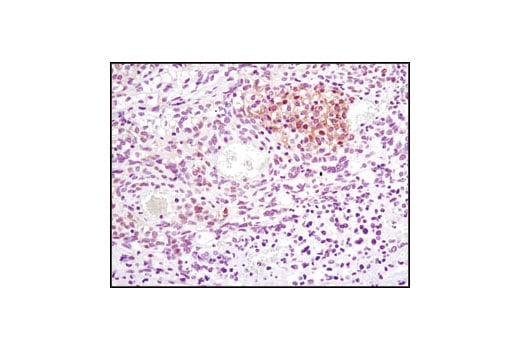

Immunohistochemical analysis of paraffin-embedded human lymphoma using FoxO1 (C29H4) Rabbit mAb. Data were generated using the standard formulation of this product.

Immunohistochemistry Image 1: FoxO1 (C29H4) Rabbit Monoclonal Antibody (BSA and Azide Free)